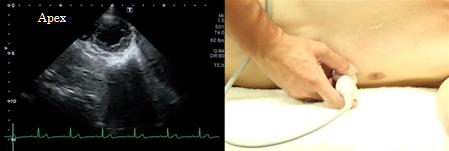

Apex level

At the apex level of the short axis view of the left ventricle, the image of the left ventricle should form a perfect circle. This view is used for evaluation of wall motion abnormalities. Since lesions confined to the apex can easily be missed, confirm the screen until the left ventricular cavity becomes invisible on the scanned image.